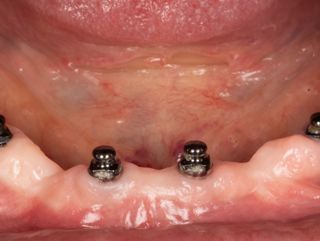

Dr Nicolas JUNG, France Thanks to the mini implant system, this patient was able to benefit from a solution that was immediately stabilised by loading the modified prosthesis post-operatively. Read more